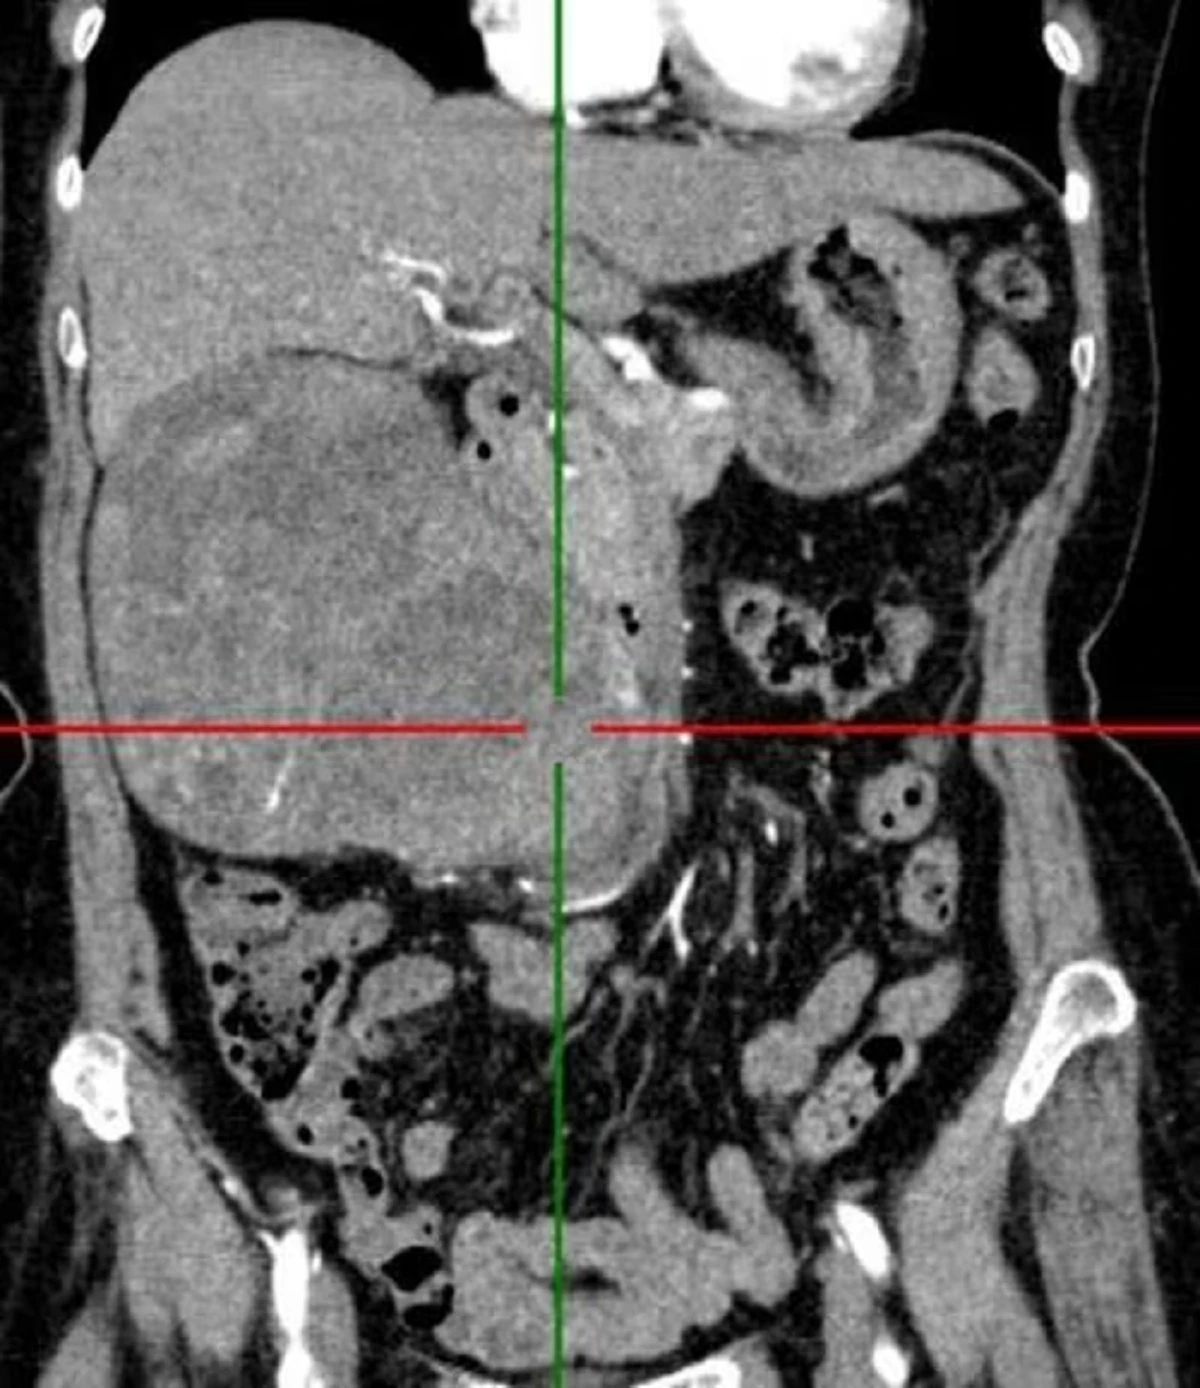

Khai thác tiền sử bệnh cụ bà 72 tuổi nhập viện vì đau âm ỉ vùng hông lưng phải kéo nhiều tháng nay. Sau khi thăm khám và làm xét nghiệm các bác sĩ kết luận nữ bệnh nhân u thận phải.

Tại viện sau hội chẩn khoa, ê-kíp đã quyết định can thiệp phẫu thuật phù hợp, loại bỏ hoàn toàn khối u cho người bệnh. Các bác sĩ Khoa Ngoại thận – Tiết niệu và Nam học, Bệnh viện đa khoa tỉnh Tuyên Quang đã cắt bỏ khối lượng u to, trọng lượng 1,2kg cho bệnh nhân.